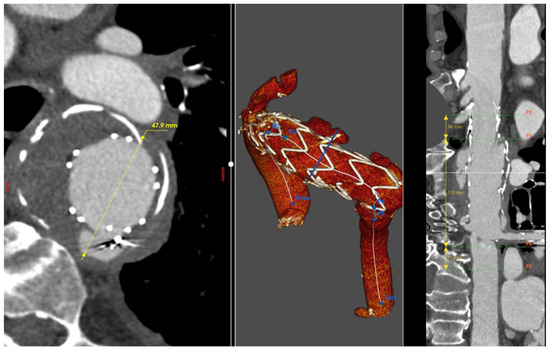

Figure 2.

Patient 2’s 3D reconstruction showing the right common carotid–left common carotid and left common carotid–left subclavian artery bypass and the type IA endoleak (blue arrow) (A). In panel (B), the result of the treatment with a custom-made solution with a landing zone in Zone 0 and a single branch for the innominate artery.

A 77-year-old gentleman with an aortic arch aneurysm underwent Thoracic Endovascular Aortic Repair (TEVAR) in Ishimaru Zone 1 and concomitant extra-anatomical bypass between the right and left common carotid and left subclavian arteries in 2011. He was subsequently lost at follow-up, although he turned up years later with an imaging investigation showing a type I endoleak in the context of a severe pseudoaneurysm formation, 72 × 130 mm, expanding around the aortic arch. A rich medical history developed over the years made the condition more challenging to treat. Endovascular intervention was considered more appropriate compared to a high-risk surgical procedure with significant potential for a fatal outcome. Given that cerebral circulation was sustained by the single innominate artery, managing this branch was crucial in planning the intervention. A prosthesis was required to ensure adequate flow through the supra-aortic branch and address the endoleak while fitting the anatomy of the aortic arch [5]. TEVAR with a custom-made prosthesis, featuring a proximal landing zone in Zone 0, an inner branch for the innominate artery, and concomitant stenting of the artery itself, was the chosen approach (Terumo, Custom Relay Pro 42-36 × 180 mm).

The wide proximal landing zone in a non-dilated ascending aorta effectively blocked blood leakage from the pseudoaneurysm. Meanwhile, stenting of the innominate artery ensured patency of the supra-aortic branches and prevented potential new endoleaks through the prosthesis fenestration. Post-procedure CTA demonstrated complete endoleak exclusion, with normal vascularization of the supra-aortic branches and no evidence of additional endoleaks, resulting in a positive outcome for the patient (Figure 2).